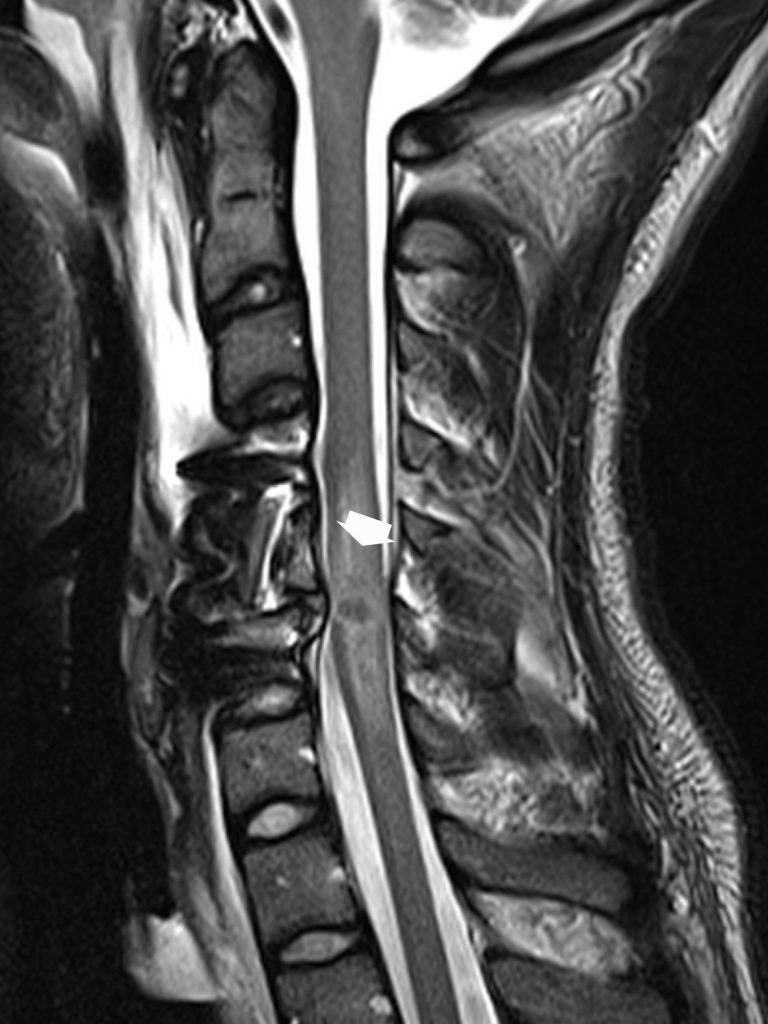

L’IRM recherche une contusion médullaire, qui se traduit par un élargissement fusiforme lié à un œdème (hypo-intense en T1 et hyperintense en T2) souvent associé des remaniements hémorragiques hypo-intenses en écho de gradient (figure 86.3). L’importance des remaniements hémorragiques est corrélée à la gravité du tableau clinique initial et est de pronostic défavorable. Elle précisera la nature de la compression qui pourra être osseuse, hématique ou discale.

Fig. 86.3 IRM (coupe sagittale T2).Réalisée après ostéosynthèse d’une fracture instable de C5, montrant une contusion médullaire en hypersignal T2 (flèche large), qui explique la tétraplégie post-traumatique.

Source : CERF, CNEBMN, 2022.